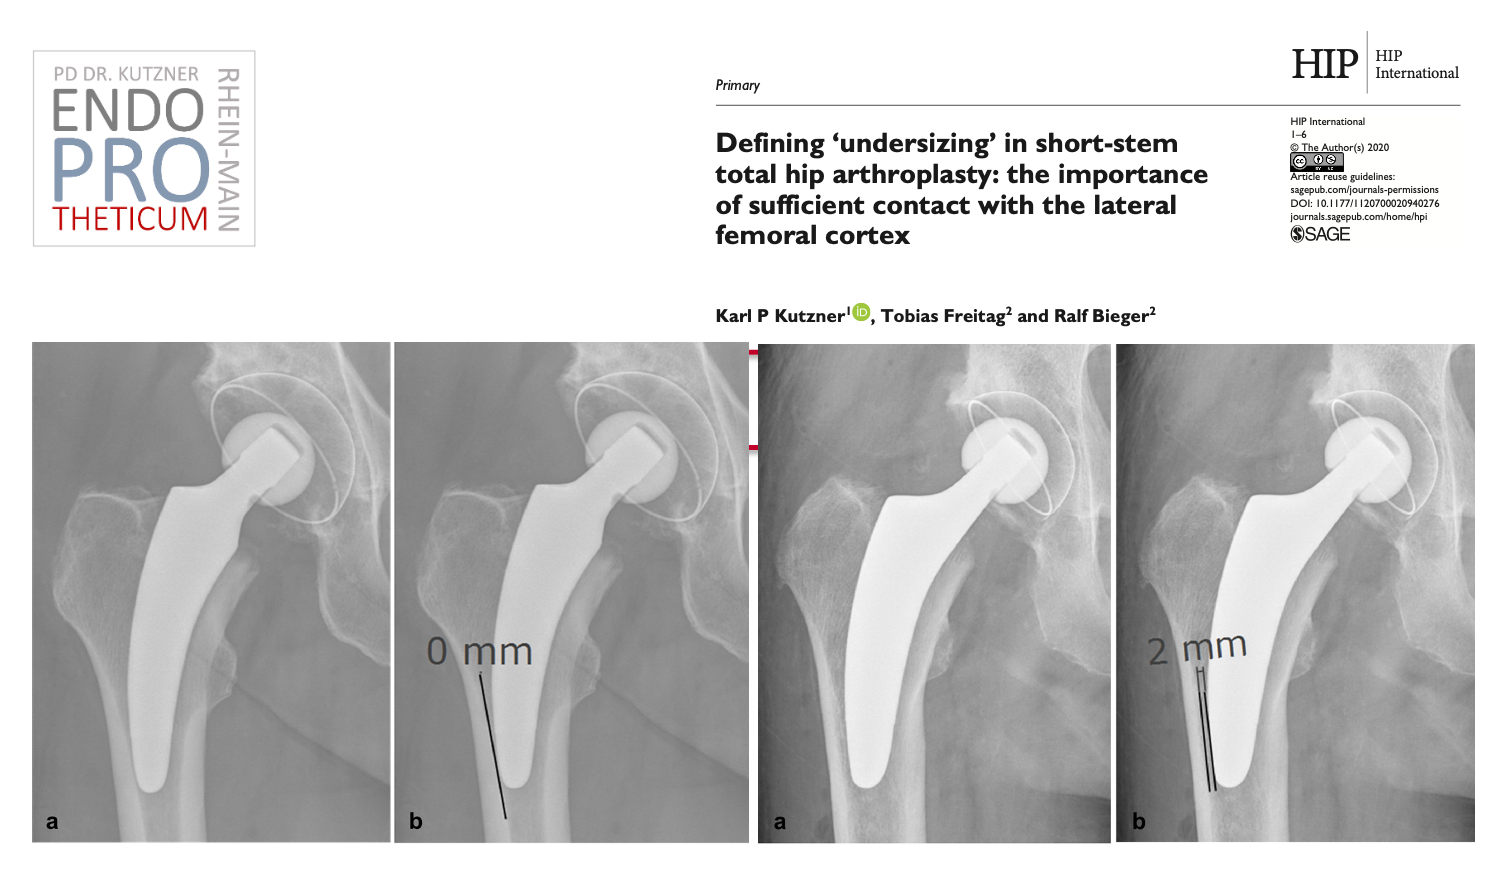

The concept of modern calcar-guided short stems in hip arthroplasty aims at the precise reconstruction of the individual, anatomical hip geometry. A bone and soft tissue-sparing implantation technique is used in conjunction with a physiological load in the part of the femur near the joint in order to preserve the bone in the long term.